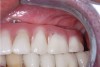

Fig 11. Preoperative close-up retracted facial view revealed extensive and unesthetic mandibular tooth wear.

Figure 11

Fig 12. Preoperative radiograph revealed the location and spacing of previously placed implants.

Figure 12

A 74-year-old woman was referred for treatment of extensive and unesthetic wear of her mandibular teeth (Figure 11 and Figure 12). Her left posterior tooth and right posterior and premolar teeth were implants; three different implant systems had been previously placed by the same dentist on the same day. Her maxillary teeth had been previously restored with zirconia full-coverage restorations.